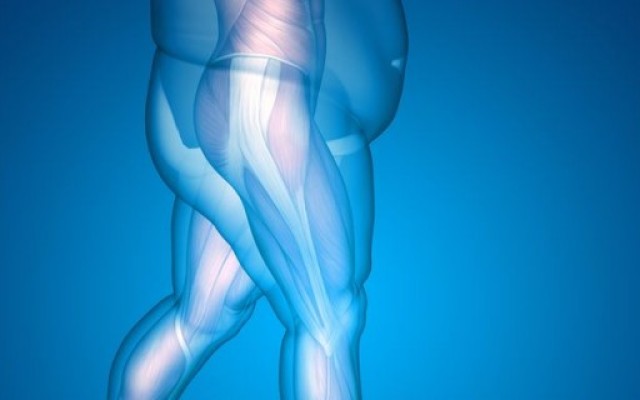

Obesity is major problem facing our affluent society. In 2014-2015, a staggering 63.4 percent of Australian adults were overweight or obese -- well over half of our nation's population. That's almost two in three adults. This is an increase from 1995, which was 56.3 percent, illustrating that the problem is getting worse.

Orthopaedic surgery deals with the treatment...